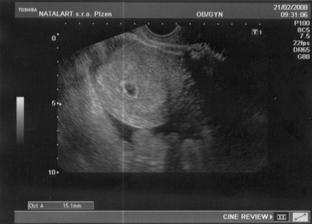

21.2. - šla jsem na první kontrolu, Zdenda musel do Berouna vyzvednout rozbité auto, tak dorazil k lékaři později - Bušilo mi srdíčko, jestli bude vše v pořádku a bylo!!! V autě jsme si pak společně prohlíželi s dojetím první fotku našeho miminka - byl to zatím jen gestační váček